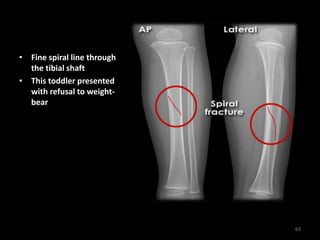

• Fine spiral line through

the tibial shaft

• This toddler presented

with refusal to weight-

bear